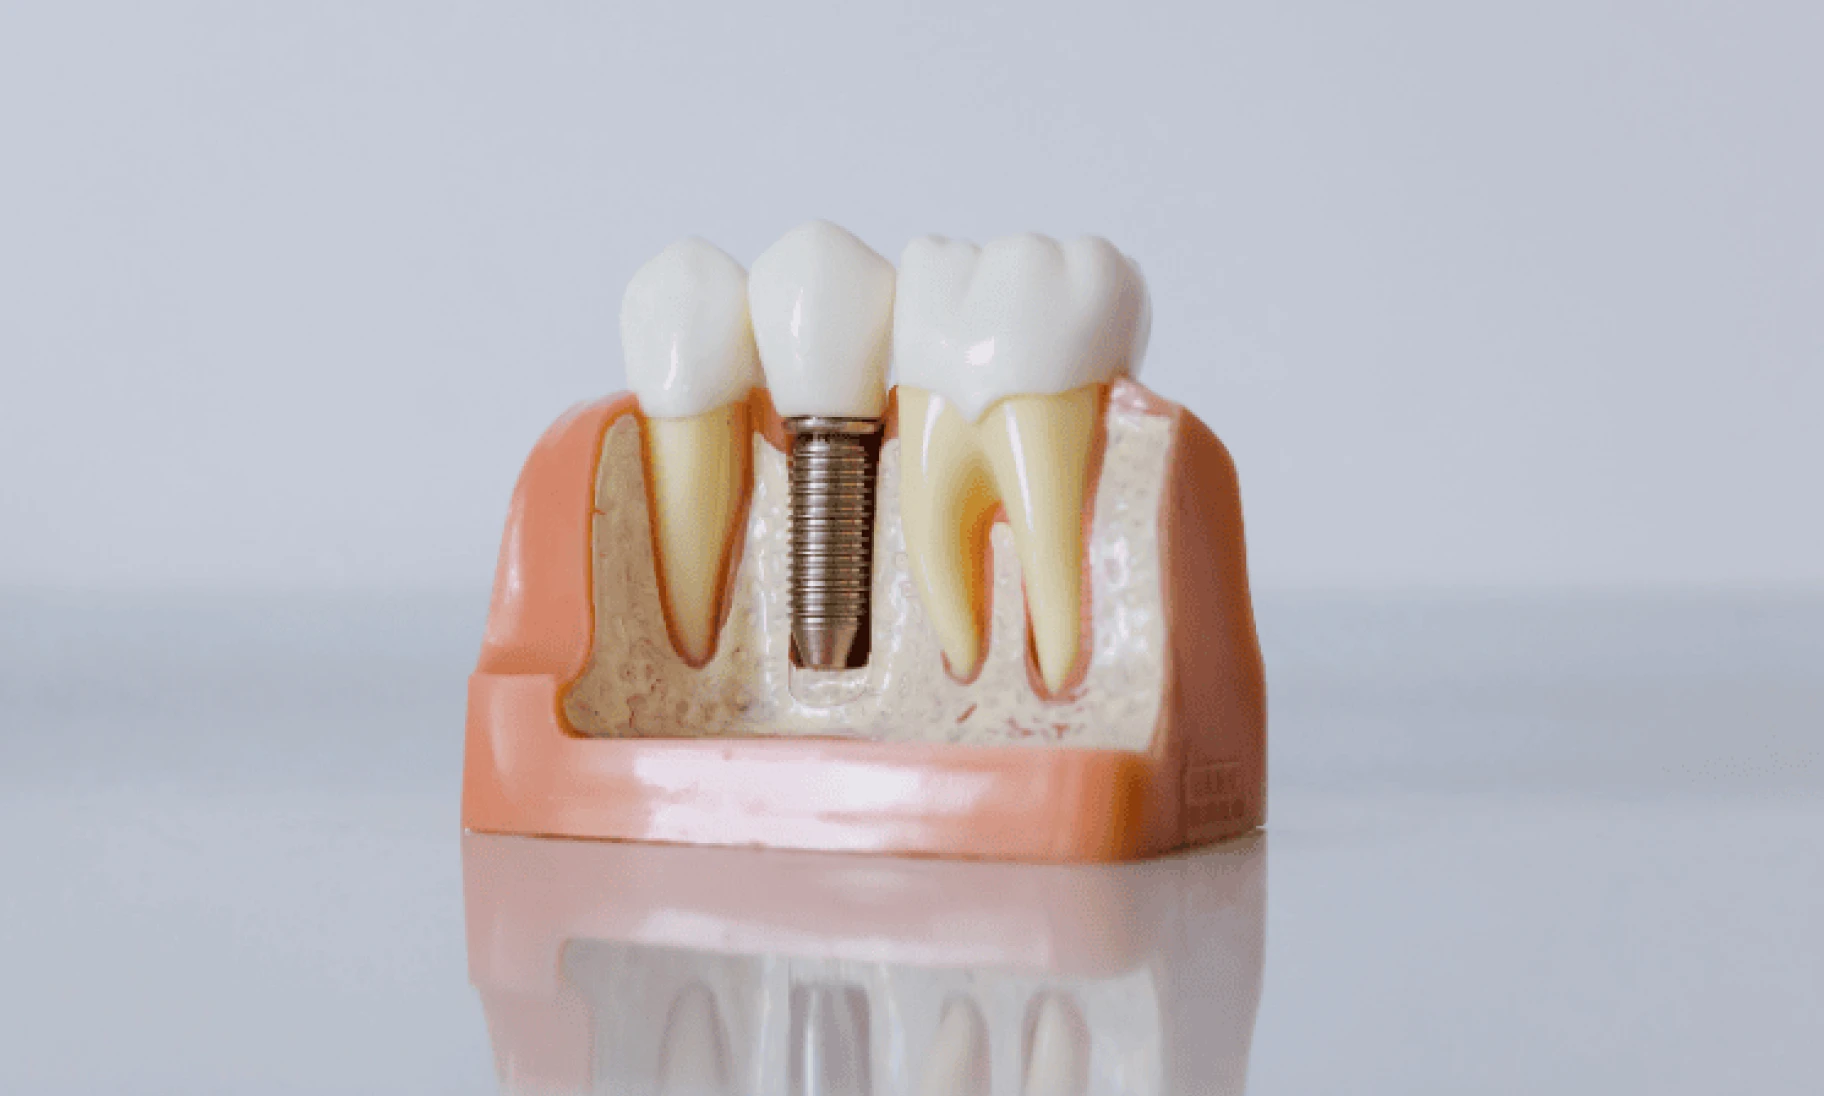

implant dentaire blog Dr Benichou Toulouse

Implant dentaire : notre guide